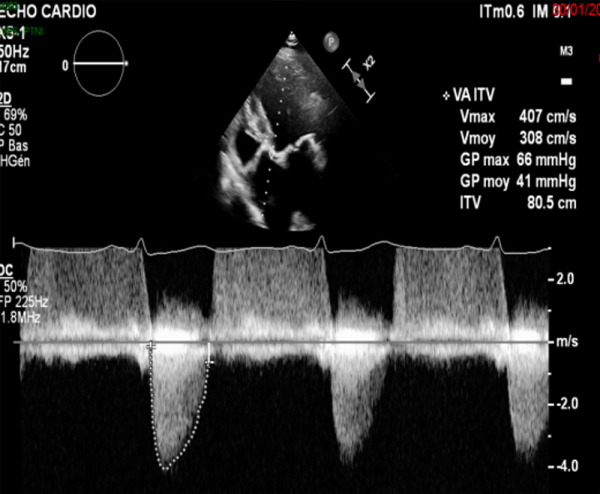

- Maladie aortique sur valve tricuspide avec RAC serré (V max 4,1 m/s, gradient moyen 41 mmHg, IP 0,27, surface 0,95 cm²) et IA modérée (grade 2)